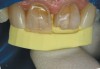

Fig 12. VPS custom lingual template for restoration of incisal edge fractures on teeth Nos. 8 and 9.

Figure 12

Fig 13. Initial build-up of lingual surface with nanohybrid composite resin using VPS template.

Figure 13

Fig 14. Completed restoration of tooth No. 8 MIFL. The next step is to finish and polish tooth No. 8 before restoring tooth No. 9 using the same VPS custom lingual guide.

Figure 14